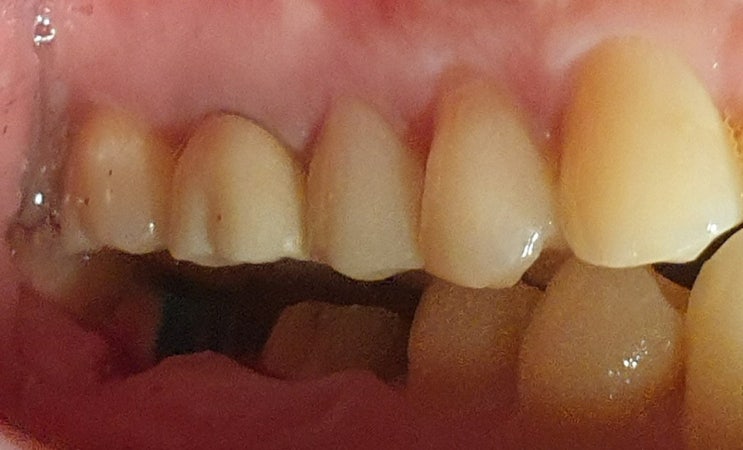

임플란트는 최후의 선택 - 치아 반측절제술 (치근절제술, 헤미섹션, hemisection)로 하악 대구치 살려쓰기

오른쪽 아래 하악제2대구치에 염증이 크게 잡혀서 발치진단을 받았습니다. 요즘은 제가 다른 치과에서 발치...